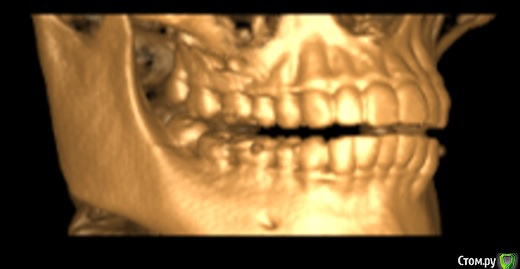

Мне 25 лет. Три месяца назад на НЧ начал расти восьмой зуб с левой стороны. Все проходило без осложнений. Но примерно две недели назад я заметила, что 3 и 4 зубы с той строны начали кривиться. До этого жалоб на прикус никогда не было, зубы были нормальные.

Паралельно с этим два месяца назад было начато лечение 7ого зуба с той же стороны.  Зуб с проблемными каналами в которых, как обнаружилось в ходе лечения, предыдущий врач оставил зацементированый инструмент.  Когда я сообщила доктору о проблеме с искривлением, был назначен прием с присутствием ортодонта.

Стоматолог предлагал вариант удаления проблемной мертвой 7ки и вытягивание на его место 8ки(она здорова и в хорошем состоянии, из десны торчит половинка), но ортодонт категорично ответила, что это невозможно.

Вердикт ортодонта - имеется легкая скученность спереди, удалить обе 8ки на НЧ, на 7ку керамическая коронка и ровнять брекетами.

К сожалению снимков до искривления нет. Но есть свежая 3D комп.томография I-CAT.  Приложу любые нужные ракурсы.